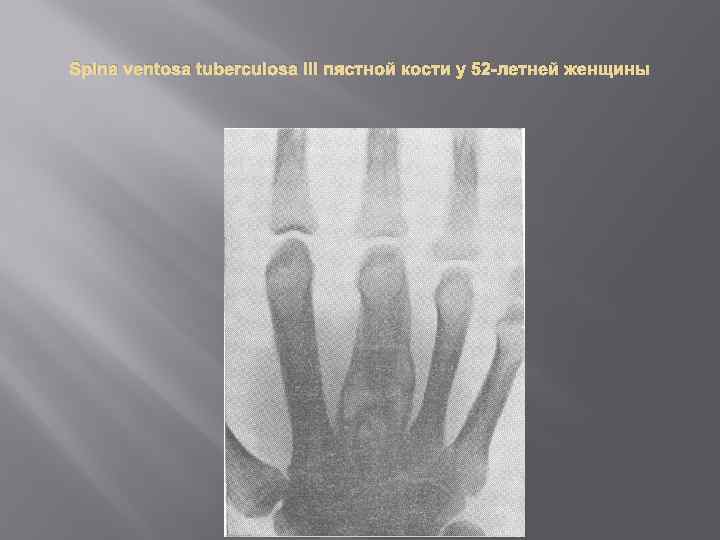

Поражение спинного мозга при туберкулезном спондилите наблюдается в случае прогрессирования туберкулезного процесса в позвоночнике, чаще в его грудном отделе. Вследствие разрушения и смещения позвонков, развития грануляционной ткани и образования натечного абсцесса, из которого казеозные массы распространяются под заднюю продольную связку позвоночника, может произойти сдавление спинного мозга и питающих его сосудов. При этом возникают расстройства кровообращения, эндофлебиты, тромбозы, специфический васкулит, что приводит к развитию отека спинного мозга и компрессионного миелита. Твердая оболочка спинного мозга препятствует распространению туберкулезного процесса на ткань спинного мозга. Очень редко патологический процесс непосредственно переходит на твердую оболочку спинного мозга (пахименингит). В редких случаях микобактерии туберкулеза заносятся в диафизы трубчатых костей и вызывают их воспаление. Эту форму болезни называют spina ventosa (вздутая ость). Туберкулезный очаг в диафизе приводит к разрастанию надкостницы и веретенообразному утолщению кости, затем наступает некроз костной ткани с образованием секвестров, при вовлечении в процесс мягких тканей формируются натечные абсцессы, свищи. Туберкулезно-аллергическое поражение суставов (болезнь Понсе) относят к параспецифическим проявлениям хронически текущего (иногда нераспознанного) туберкулеза легких, плевры, лимфатических узлов и других органов. Воспаление синовиальной оболочки и других тканей суставов в этих случаях является аллергическим (иммунным) и не имеет специфической морфологической картины. Обычно поражается несколько суставов (полисиновит или полиартрит Понсе).

Поражение спинного мозга при туберкулезном спондилите наблюдается в случае прогрессирования туберкулезного процесса в позвоночнике, чаще в его грудном отделе. Вследствие разрушения и смещения позвонков, развития грануляционной ткани и образования натечного абсцесса, из которого казеозные массы распространяются под заднюю продольную связку позвоночника, может произойти сдавление спинного мозга и питающих его сосудов. При этом возникают расстройства кровообращения, эндофлебиты, тромбозы, специфический васкулит, что приводит к развитию отека спинного мозга и компрессионного миелита. Твердая оболочка спинного мозга препятствует распространению туберкулезного процесса на ткань спинного мозга. Очень редко патологический процесс непосредственно переходит на твердую оболочку спинного мозга (пахименингит). В редких случаях микобактерии туберкулеза заносятся в диафизы трубчатых костей и вызывают их воспаление. Эту форму болезни называют spina ventosa (вздутая ость). Туберкулезный очаг в диафизе приводит к разрастанию надкостницы и веретенообразному утолщению кости, затем наступает некроз костной ткани с образованием секвестров, при вовлечении в процесс мягких тканей формируются натечные абсцессы, свищи. Туберкулезно-аллергическое поражение суставов (болезнь Понсе) относят к параспецифическим проявлениям хронически текущего (иногда нераспознанного) туберкулеза легких, плевры, лимфатических узлов и других органов. Воспаление синовиальной оболочки и других тканей суставов в этих случаях является аллергическим (иммунным) и не имеет специфической морфологической картины. Обычно поражается несколько суставов (полисиновит или полиартрит Понсе).

Spina ventosa (туберкулез диафизов трубчатых костей) встречается редко, преимущественно у детей. Патологический процесс локализуется чаще в коротких трубчатых костях кисти (фаланги пальцев, пястные кости) и стопы (плюсневые кости). Среди длинных трубчатых костей поражаются главным образом кости предплечья и большеберцовая кость. три фазы болезни: • перифокальную • секвестрации • свищевую Для подтверждения туберкулезной природы болезни используют общефтизиатрические методы, туберкулинодиагностика, бактериологическое исследование отделяемого свища

Spina ventosa (туберкулез диафизов трубчатых костей) встречается редко, преимущественно у детей. Патологический процесс локализуется чаще в коротких трубчатых костях кисти (фаланги пальцев, пястные кости) и стопы (плюсневые кости). Среди длинных трубчатых костей поражаются главным образом кости предплечья и большеберцовая кость. три фазы болезни: • перифокальную • секвестрации • свищевую Для подтверждения туберкулезной природы болезни используют общефтизиатрические методы, туберкулинодиагностика, бактериологическое исследование отделяемого свища

В перифокальной фазе (периостальная реакция диафиза кости в зоне расположения туберкулезного очага) в области поражения наблюдается веретенообразная припухлость, слегка болезненная при пальпации, кожа над ней не изменена. Общее состояние больного может не нарушаться. На рентгенограмме выявляют равномерное остеопериостальное утолщение и небольшие очаги просветления (деструкции) в костной ткани. В фазе секвестрации припухлость в зоне поражения нарастает, появляются отечность мягких тканей, боли, увеличиваются регионарные лимфатические узлы, температура тела повышается до субфебрильной. На рентгенограмме обнаруживают большую зону просветления, нанимающую иногда весь диафиз, с участками затенения (секвестры), резко выраженную периостальную реакцию, в мягких тканях, окружающих кость, выявляют уплотнение Свищевая фаза характеризуется формированием наружных свищей, патологических переломов, вывихов фаланг. Рентгенологически определяются фрагментация секвестра, разрушение компактного костного вещества. При вторичном инфицировании свищей состояние больного ухудшается, температура тела повышается.

В перифокальной фазе (периостальная реакция диафиза кости в зоне расположения туберкулезного очага) в области поражения наблюдается веретенообразная припухлость, слегка болезненная при пальпации, кожа над ней не изменена. Общее состояние больного может не нарушаться. На рентгенограмме выявляют равномерное остеопериостальное утолщение и небольшие очаги просветления (деструкции) в костной ткани. В фазе секвестрации припухлость в зоне поражения нарастает, появляются отечность мягких тканей, боли, увеличиваются регионарные лимфатические узлы, температура тела повышается до субфебрильной. На рентгенограмме обнаруживают большую зону просветления, нанимающую иногда весь диафиз, с участками затенения (секвестры), резко выраженную периостальную реакцию, в мягких тканях, окружающих кость, выявляют уплотнение Свищевая фаза характеризуется формированием наружных свищей, патологических переломов, вывихов фаланг. Рентгенологически определяются фрагментация секвестра, разрушение компактного костного вещества. При вторичном инфицировании свищей состояние больного ухудшается, температура тела повышается.